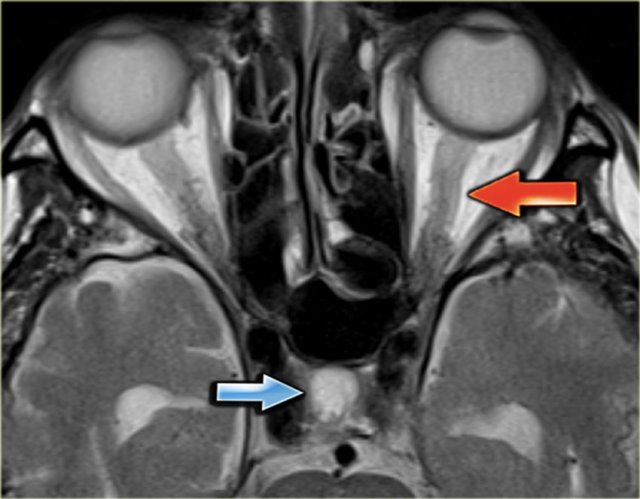

On the left a T2-weighted image with normal flow void in the right sigmoid sinus and jugular vein (blue arrow).

On the left there is abnormal high signal as a result of thrombosis (red arrow).